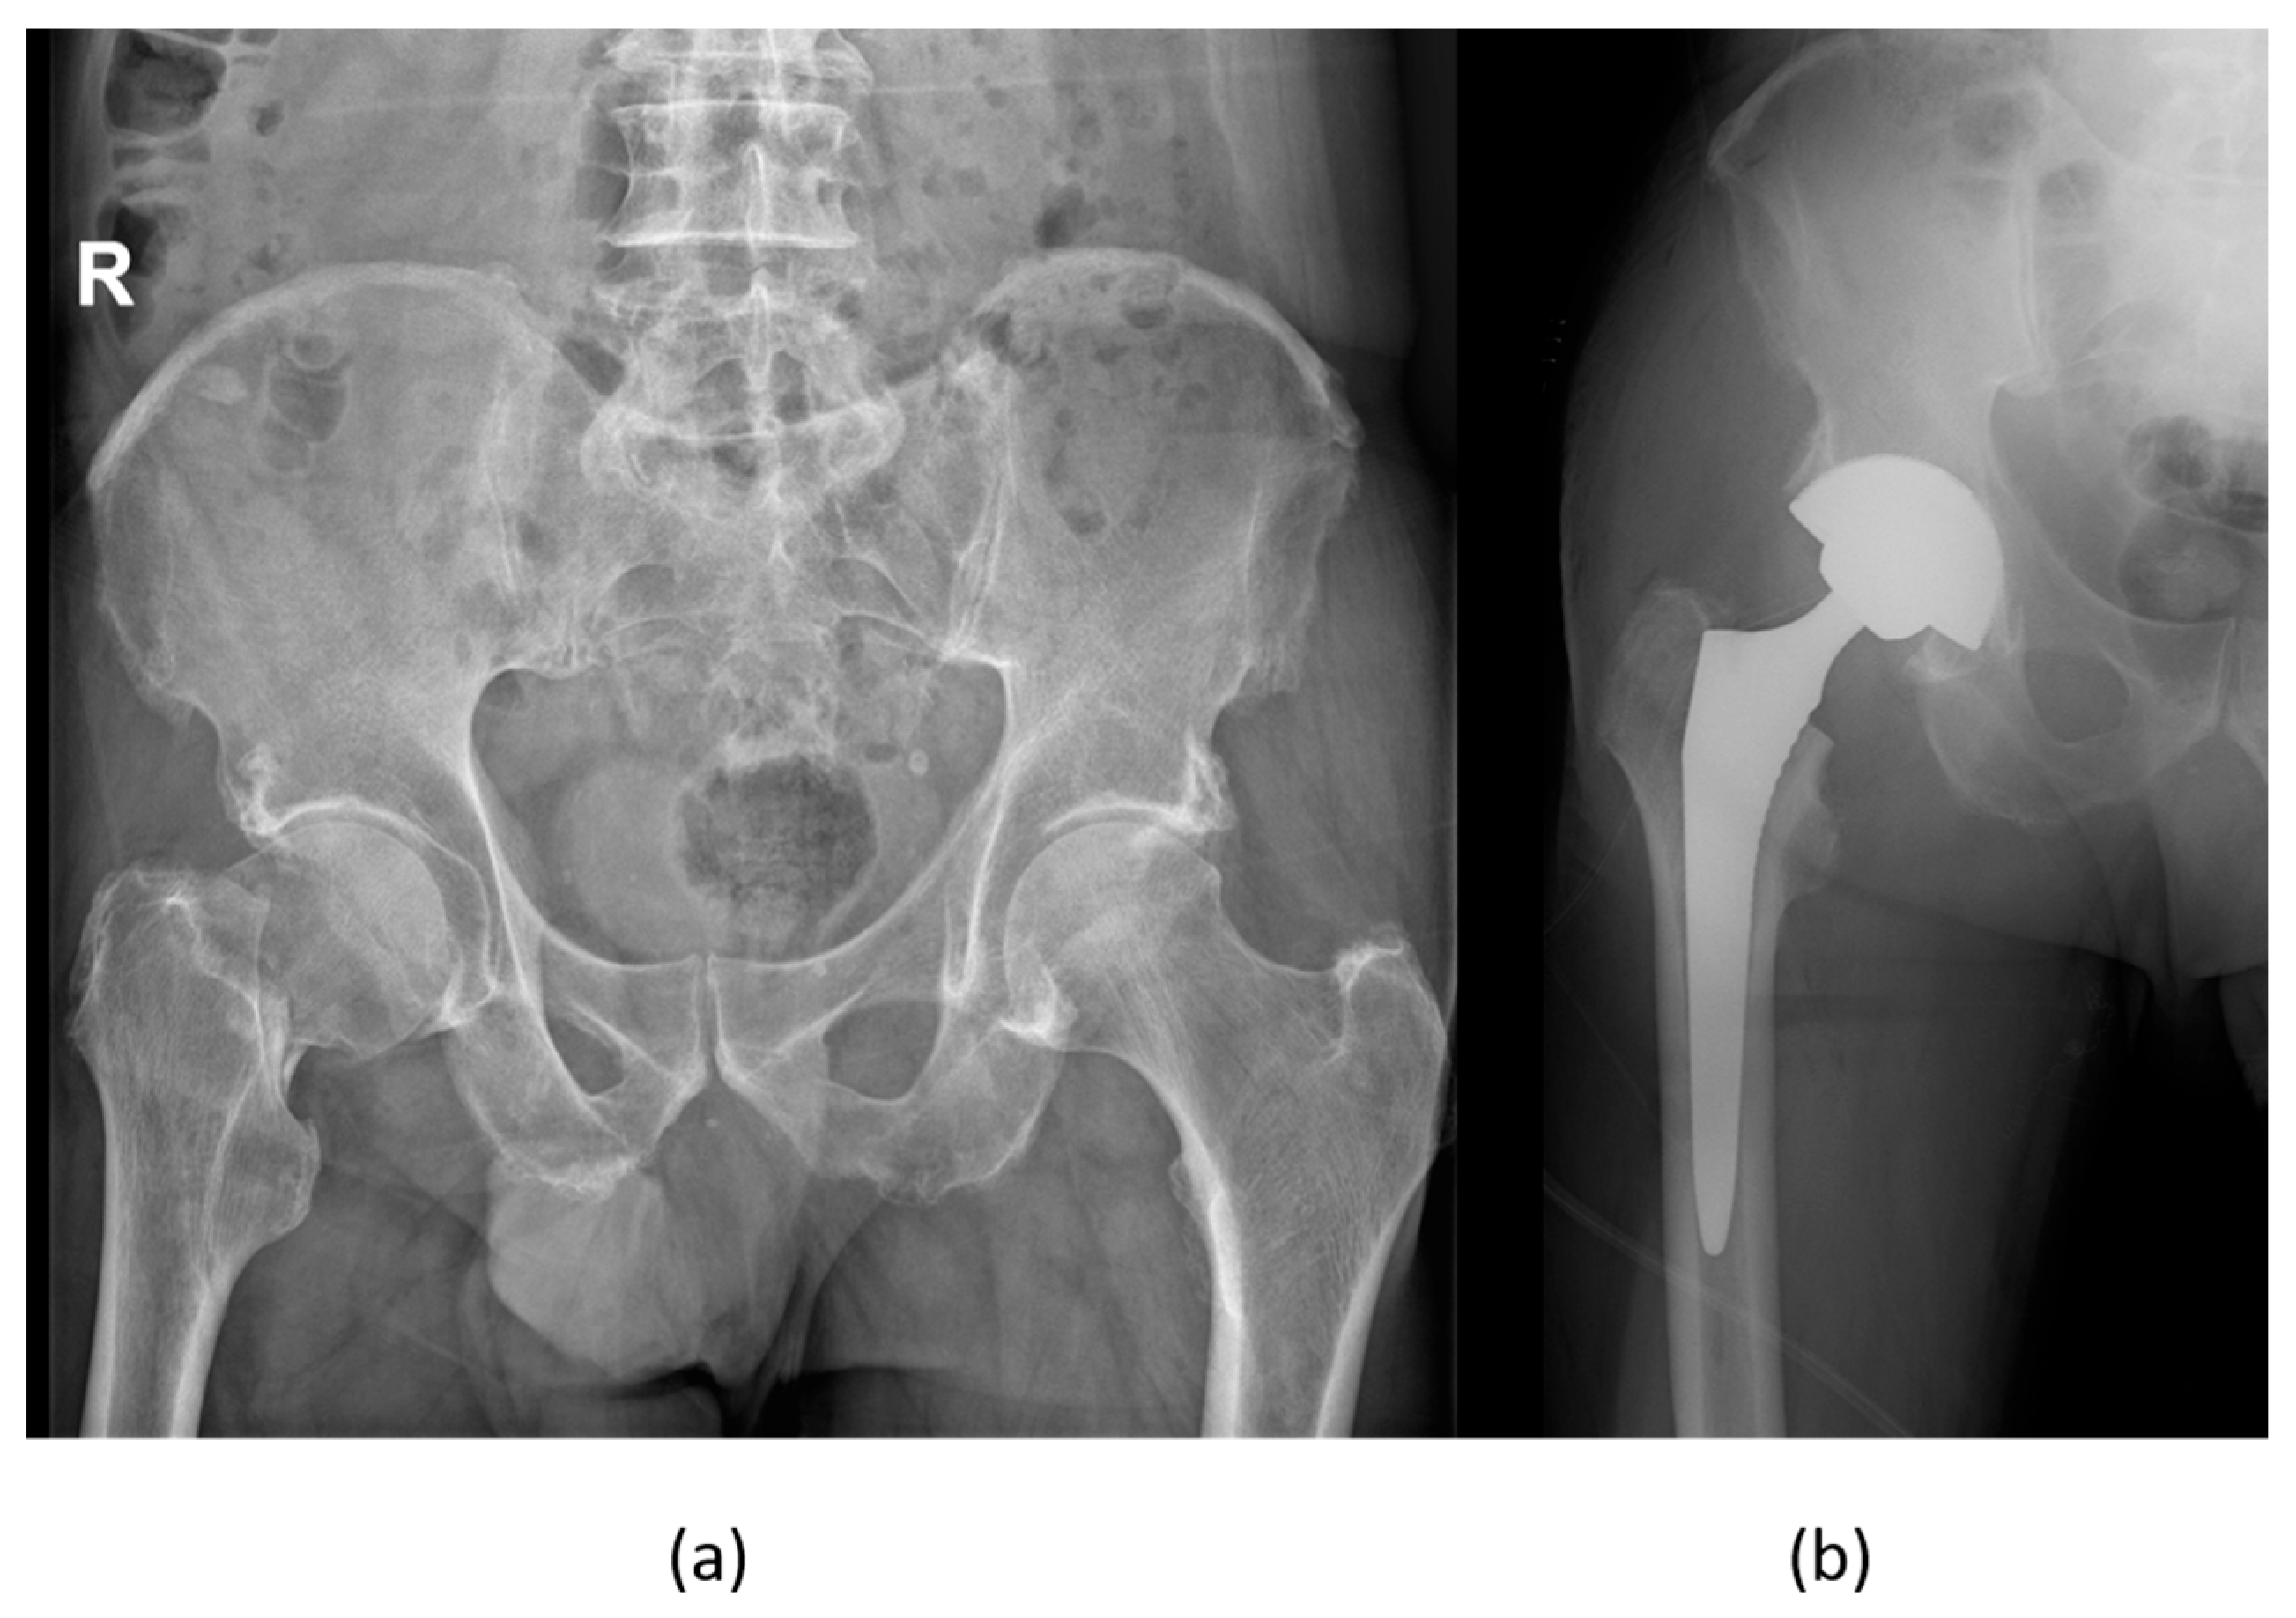

8. Orthopedic Management of Sexual Minority Individuals

Clinicians should be attentive to the needs of sexual minority individuals, including members of the LGBTQIA+ community and men having sex with men (MSM) [90,91]. These populations have been disproportionately impacted and are still impacted by the HIV pandemic. People living with HIV (PLWHIV) suffer from bone mineralization abnormalities, including osteoporosis and osteopenia [92] (Figure 6), the etiopathogenesis of which depends on various factors related to the host, the virus, and the specific regimen of antiretrovirals used, and their complex, non-linear interplay [93].

Recent advancements in combined antiretroviral therapy (cART) have significantly changed the management of HIV infection, turning it into a manageable chronic condition that increases life expectancy. This shift means orthopedic surgeons are more likely to treat PLWHIV in their practices. Musculoskeletal symptoms are often seen in individuals with HIV, sometimes as the first sign of the infection, making it crucial for surgeons to be knowledgeable about related neoplasms and conditions affecting the muscles, bones, and joints for effective treatment. With the introduction of cART, procedures like total joint arthroplasty have become safer, though there remains a minor risk of perioperative infection, particularly in patients with uncontrolled HIV or CD4 counts below 400 cells/mm3. In trauma surgery, while the risk of infection around implants and the rates of bone healing in PLWHIV are similar to those in HIV-negative individuals (Figure 7), there is a heightened risk of complications such as pulmonary, renal, and infectious or septic issues in cases of severe trauma. For optimal patient care outcomes, factors including CD4 count, nutritional status, adherence to cART, viral load, and other conditions like hemophilia or infections from intravenous drug use must be considered when managing PLWHIV [93].